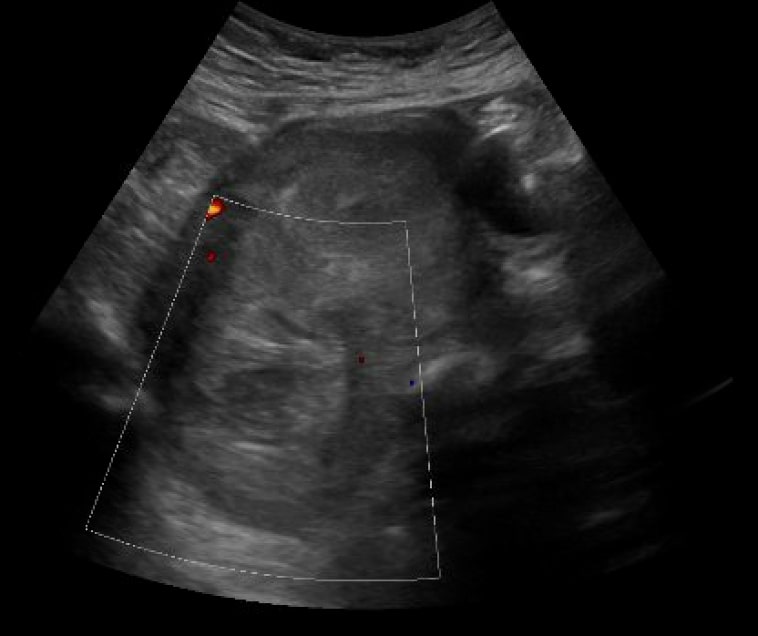

Uterine perforation is a rare but potentially life-threatening complication of gynecologic procedures. Serious complications include hemorrhage, infection, and injury to surrounding organ systems (eg, gastrointestinal, urological, vascular, etc.). Risk factors include advanced maternal age, prior gynecologic surgeries, and other anatomical features that impact the difficulty of accessing the uterine cavity. In this case report, we discuss a patient who presented to the emergency department (ED) with diffuse abdominal pain and vaginal bleeding that occurred after an elective dilation and curettage (D&C) for a termination of pregnancy. The diagnosis was suspected clinically and confirmed by imaging including ultrasound (US) and computed tomography (CT) of the abdomen and pelvis. The patient was managed operatively with a multidisciplinary approach including Gynecology, General Surgery, and Urology. The patient was stabilized and eventually discharged. Uterine perforation should be included in the differential for patients with a history of recent gynecologic instrumentation presenting with abdominal pain and vaginal bleeding. The stabilization of these patients requires aggressive volume resuscitation, controlling the source of bleeding, and emergent surgical consultation.

Topics: Gynecology, vaginal bleeding, ultrasound, computed tomography.